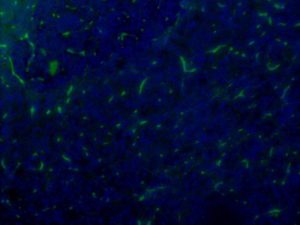

CAT NO: ABS 023-02 | Application: ELISA, WB, IHC, IF